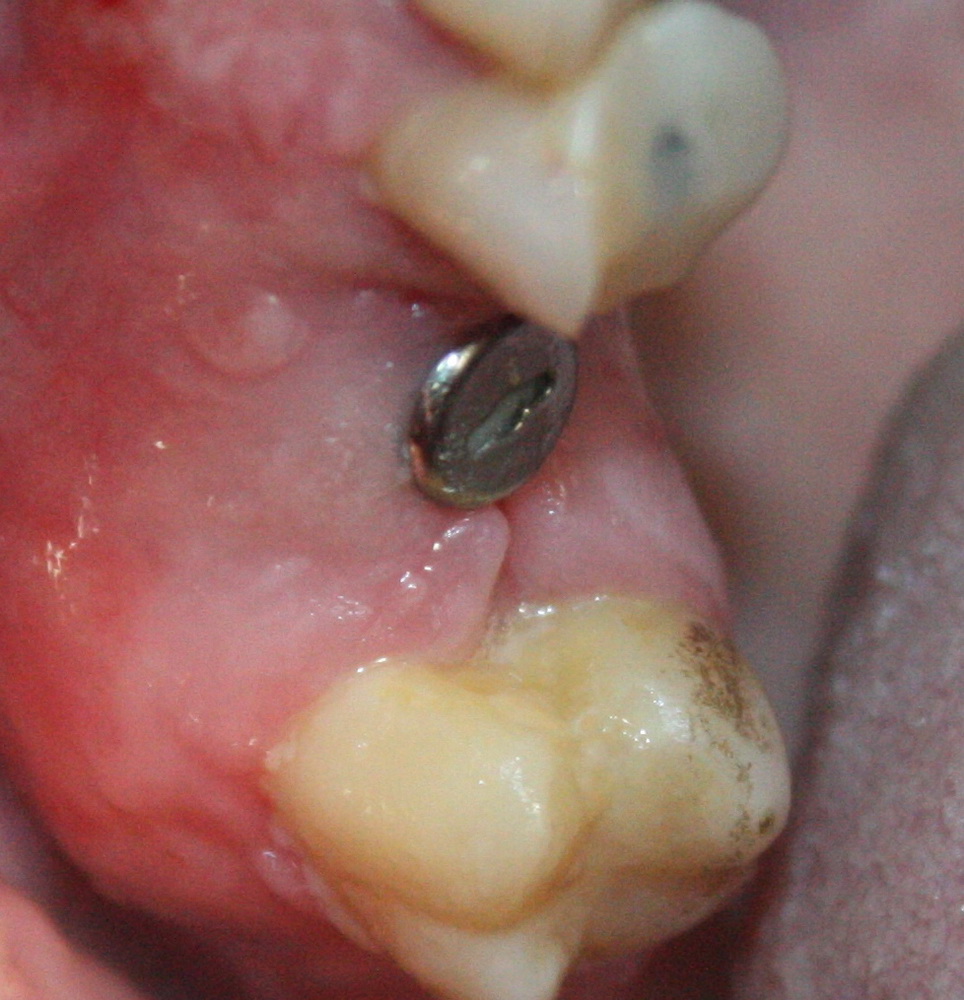

Немедленная имплантация — оптимальное решение в любой клинической ситуации